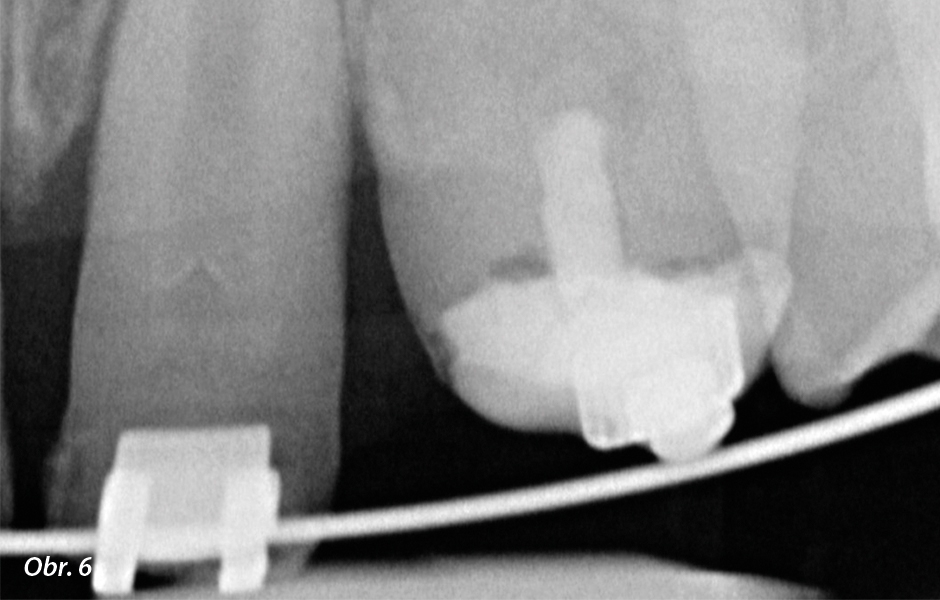

Před ošetřením pacientů s erozními defekty zubů je důležité získat jejich celkovou zdravotní anamnézu (zda se u nich nevyskytuje např. bulimie nebo reflux) a zjistit, jaké mají stravovací návyky. Je-li to možné, měl by být před ošetřením přizván ke konzultaci i jejich praktický lékař. U pacientů s kongenitálním defektem struktury zubů je nanejvýš důležité důkladné klinické a radiologické vyšetření, protože kromě sklovinných defektů (obr. 4, 5) mohou tito jedinci trpět také folikulárními cystami, vyskytuje se u nich abnormální erupce zubů, retinované zuby, otevřený skus nebo kalcifikace zubní dřeně (obr. 6–8). Porucha je navíc doprovázena gingiválním a periodontálním onemocněním. Toto je nutné vzít v potaz již při předběžném ošetření hypomineralizované a hypokalcifikované skloviny. V souvislosti se závažností poškození tvorby skloviny může být dosaženo mnohem slabší adhezivní vazby, než jaká vzniká na zdravé sklovině. Ve výsledku se musí ve většině případů adhezivní vazba zajistit na dentinu (obr. 9).